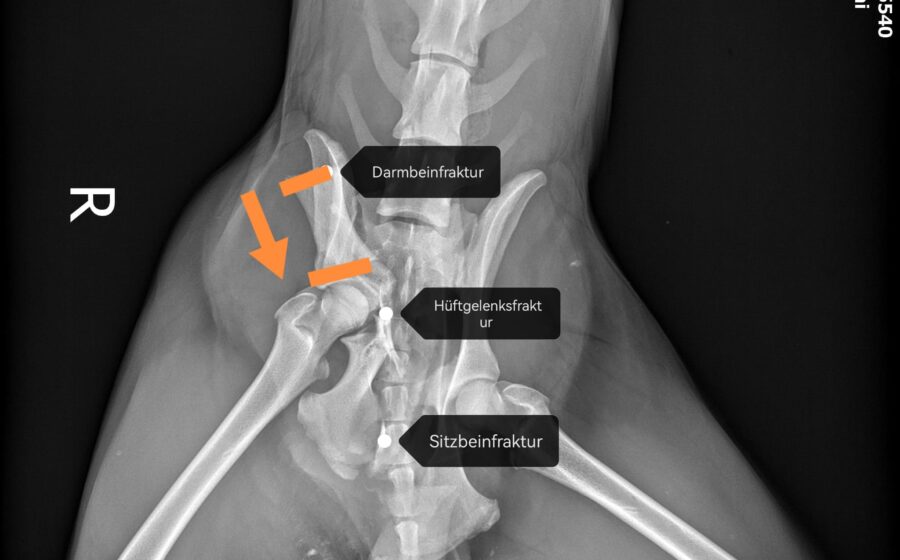

Seine Geschichte ist bewegend: Er wurde schwer verletzt am Straßenrand gefunden. Vermutlich wurde er hinter einem Auto hinterher geschleift und dann liegengelassen. Als Notfall wurde er in die Tierklinik gebracht, wo bei ihm drei Frakturen diagnostiziert wurden – am Darmbein, am Hüftgelenk und am Sitzbeinhöcker. In einer aufwendigen Operation, wurde die Darmbeinfraktur mit einer Platte fixiert. Die Hüftgelenksfraktur wurde nach Einholung zweier deutscher Ärzte-Meinungen nicht operiert, er hat einen Beckenengstand. Mit Physiotherapie wurde er soweit wieder aufgebaut, dass er jetzt mühelos 2 Stunden Spazierengehen kann. Er liebt die Bewegung und flitzt gerne durch den Garten seiner Pflegestelle.